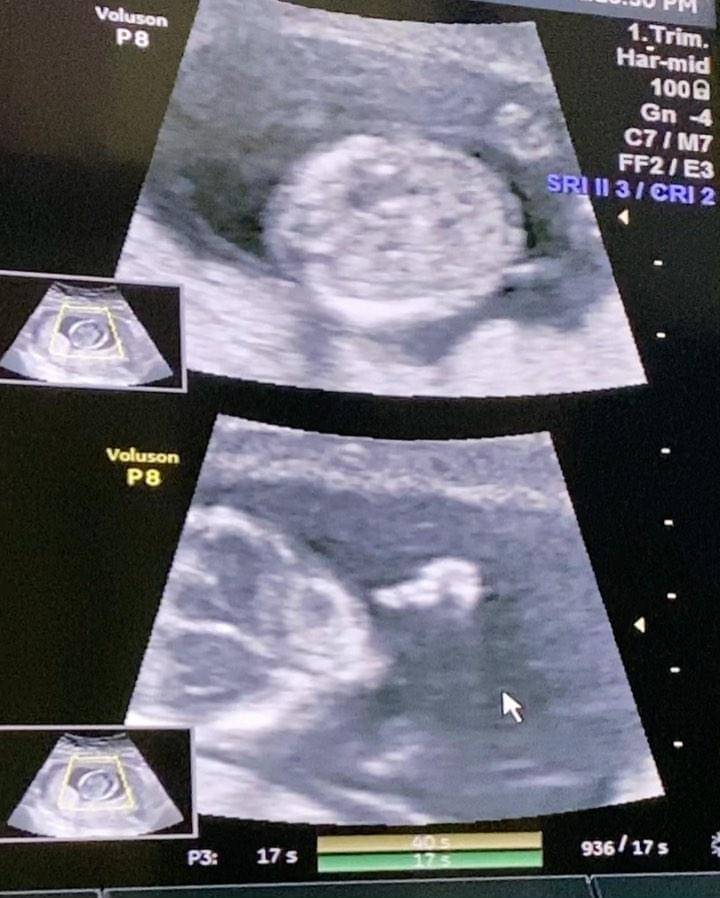

Pasangan ini berpose romantis dan memamerkan hasil foto USG janin dalam kandungan Fiona. Aktor yang naik daun berkat film 'Cek Toko Sebelah' ini mengungkapkan kebahagiaan mereka akan segera menjadi orangtua dengan kata-kata yang romantis.

Dion mengumumkan jika kehamilan Fiona sudah menginjak usia 14 minggu atau memasuki usia empat bulan. Pengumuman kehamilan di momen Hari Valentine seolah menjadi hadiah bagi keluarga dan penggemarnya.

"Happy Valentine's day from 4 of us. Puji Tuhan buah hati kami sudah berumur 14 minggu dan dalam keadaan sehat," ujar Dion di Instagramnya.

3. Dion Wiyoko sebut bayi dalam kandungan istri sudah 'joget-joget'

Disebutkan oleh aktor film 'The Gift' ini jika janin dalam kandungan Fiona sudah aktif dan bisa joged-joged. Karena hal ini pula ia senang melihat perkembangan yang aktif dari malaikat kecilnya itu.